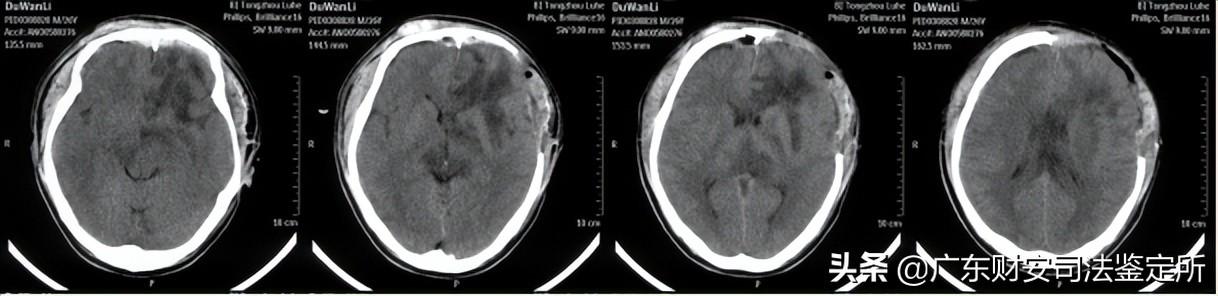

2014-6-16颅面部CT片示:双侧额骨、双眼眶壁、双侧鼻骨等颅面骨多发骨折,颅底骨折,左侧开颅术后,左侧额颞顶部分颅骨缺损,局部脑组织稍向外膨隆,颅内积气,双侧额叶可见少量高密度影,右侧额部可见金属探头,左侧额叶可见不规则大片状低密度区,左侧侧脑室稍受压,局部中线结构稍右偏。(见附件5-A)

2014-6-24颅脑CT片示:右侧额部金属探头已拔除,左侧脑室受压解除,中线结构居中,余基本同前。(见附件5-B)

2014-8-5首次术后颅脑CT片示:左侧开颅术后,额颞部分颅骨缺损,双侧额叶、左侧基底节区、侧脑室旁均可见软化灶、形态不规则,左侧侧脑室轻度扩张,中线结构居中。(见附件5-C)

2014-9-18修补术后复查颅脑CT片示:左侧额颞部颅骨减压修补术后,胼胝体、左侧基底节区可见斑片状低密度灶,双侧额叶可见不规则低密度灶,中线结构居中。(见附件5-D)

|

A、2014-6-16(伤后3天)头颅CT片 |

B、2014-6-16(伤后3天)头颅CT片 |

C、2014-8-5(伤后1个月余)头颅CT片 |

D、2014-9-18(伤后3个月)头颅CT片 |